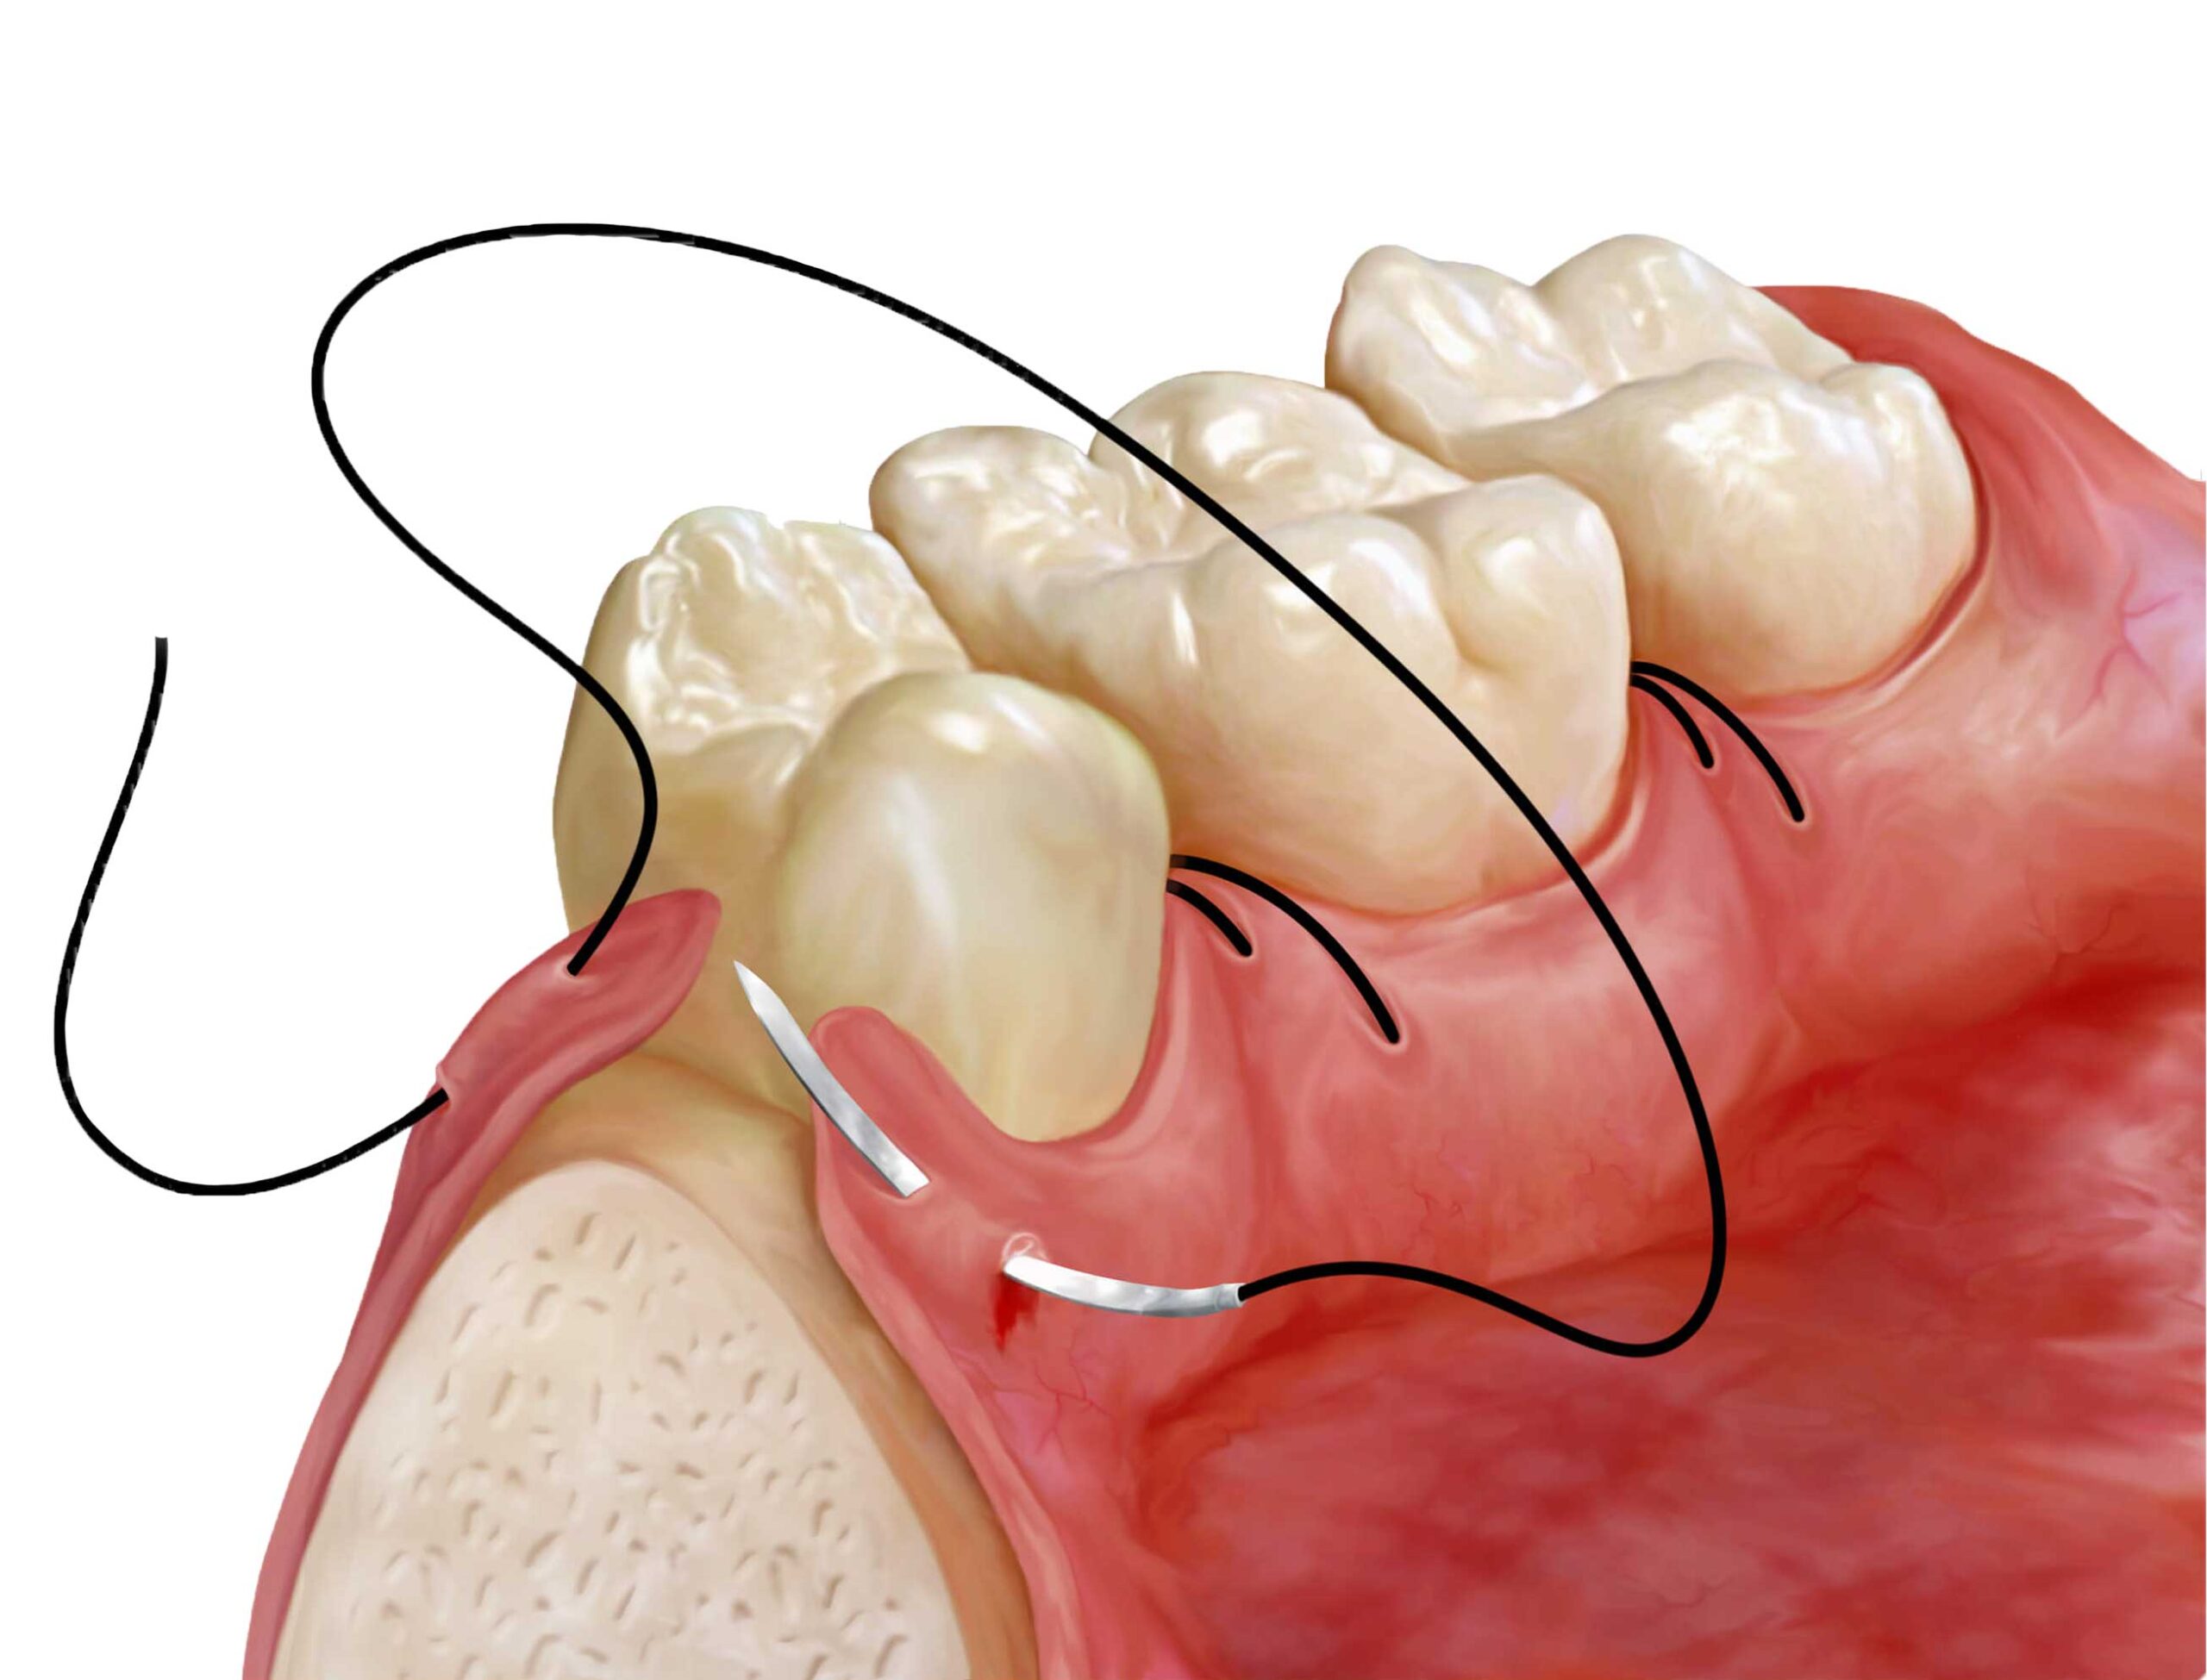

🔬Cirurgia Periodontal

de Acesso

👆 Toque para abrir

de Acesso

Quando a raspagem não alcança toda a raiz. Retalho cirúrgico para limpeza profunda, regeneração óssea guiada e enxertos em casos de perda óssea significativa.

Cirurgias periodontais — quando o acesso é necessário

Nos casos em que a raspagem subgengival não alcança toda a extensão da raiz comprometida — geralmente bolsas periodontais ≥6mm — a cirurgia periodontal é indicada. O objetivo é o acesso direto à região afetada para limpeza profunda, remoção do tecido infectado e, quando possível, regeneração das estruturas perdidas.

As cirurgias são realizadas com anestesia local, são minimamente invasivas nas mãos certas, e a recuperação é tranquila. Em centros de referência como o Harley Street de Londres e as clínicas de periodontia de Paris e Roma, a abordagem é idêntica — os protocolos são os mesmos adotados aqui em Divinópolis.